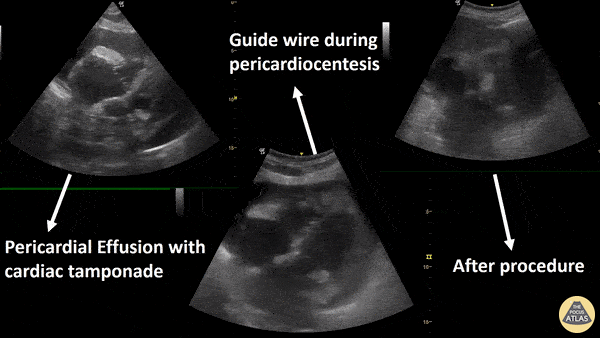

Subcostal view of a pericardial effusion with cardiac tamponade and its resolution with pericardiocentesis. Renato Melo, Pocus Jedi co-founder, @JediPocus Emergency Physician at H.C. de MarĂ­lia/SP Brazil